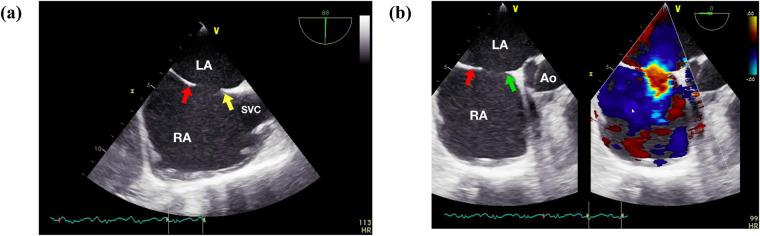

Zero-fluoroscopy, exclusively ultrasound-guided atrial septal defect (ASD) catheter closure has been reported. However, data on the effectiveness of this technique in complex cases remains limited.

This study aims to evaluate the safety, efficacy, and outcomes of ASD catheter closure using exclusive ultrasound guidance, with a particular focus on complex cases.

已有报道称可在完全超声引导下进行零荧光透视房间隔缺损(ASD)导管封堵术。然而,关于该技术在复杂病例中的有效性的数据仍然有限。

本研究旨在评估完全超声引导下ASD导管封堵术的安全性、有效性及结果,尤其关注复杂病例。